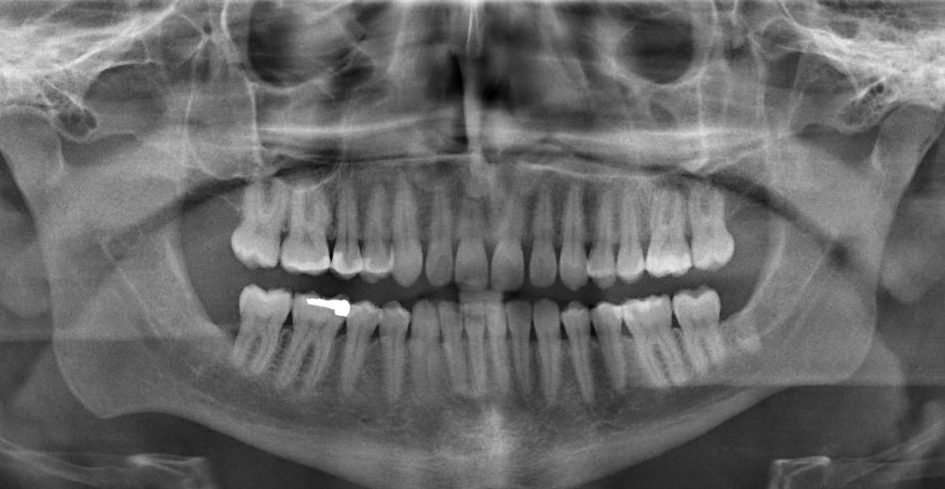

- Panoramic: Displays a view of the teeth, jaws, nasal area, sinuses and jaw joints and generally taken when a patient may need orthodontic treatment.